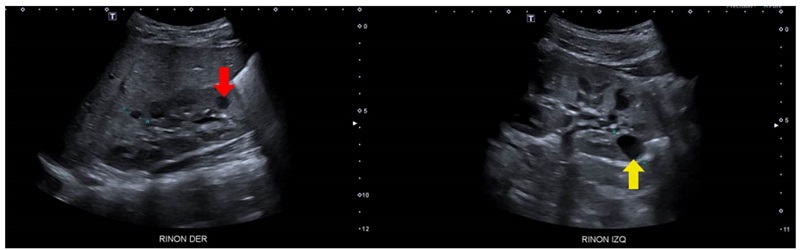

Se trató de un paciente de sexo masculino, producto de una unión consanguínea, que a los seis meses de vida presentó un episodio de pielonefritis. La ecografía renal mostró imágenes sugestivas de enfermedad poliquística renal autosómica recesiva, con múltiples imágenes quísticas bilaterales de ecogenicidad heterogénea y pérdida de la diferenciación corticomedular (figura 3). No presentaba lesiones hepáticas en la ecografía y la función hepática era normal.

Análisis. La enfermedad poliquística renal de herencia autosómica recesiva es una condición rara y de presentación usualmente grave en los primeros años de vida. Su incidencia se ha reportado como un caso por cada 26.500 recién nacidos vivos 18. Representa un espectro clínico que incluye la presencia de quistes que afectan los conductos colectores, así como nefromegalia, pérdida de la diferenciación corticomedular y fibrosis hepática; es causada principalmente por variantes bialélicas del gen de la fibrocistina (PKHD1), aunque también se han reportado variantes del gen DZIP1L (DAZ interacting protein 1-like) 19. Sin embargo, existe un gran número de síndromes con presentaciones similares (fenocopias), por lo cual se indica el diagnóstico molecular mediante secuenciación masiva paralela de múltiples genes. Se estima que en el 20 al 25 % de los pacientes no se encuentra la causa genética 20.